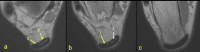

The aim of the study was to check if the subtendons of the Achilles tendon can be identified in vivo on MRI in the midportion of the tendon. The relation of the plantaris tendon to the Achilles tendon was also examined. A retrospective study of 200 MRI of ankle joints including the Achilles tendon was conducted. Statistical analysis of the correlation between the possibility of identifying the subtendons and the side, gender, presence of the central soleus tendon and plantaris tendon variation was performed. The inter-observer agreement between two reviewers in their evaluation of the subtendons was assessed using kappa statistics. The subtendon from the lateral head of the gastrocnemius muscle was identified in 65% (k = 0.63) and was located in the anterior part of the Achilles tendon. The subtendon from the soleus muscle was recognized in 12% (k = 0.75) comprising anterior part of the tendon. In 6% the subtendon from the medial head of the gastrocnemius muscle was identified (k = 0.58). The central soleus tendon was identified in 85% of cases. Statistical analysis shows the weak correlation of the presence of the central soleus tendon and the possibility of identifying the subtendon from the soleus muscle. The plantaris tendon was directly related to the insertion of the Achilles tendon in 42.5%. Identification of the subtendons of the Achilles tendon on MRI is challenging, and most often it is only possible to find the subtendon of the lateral head of the gastrocnemius muscle.